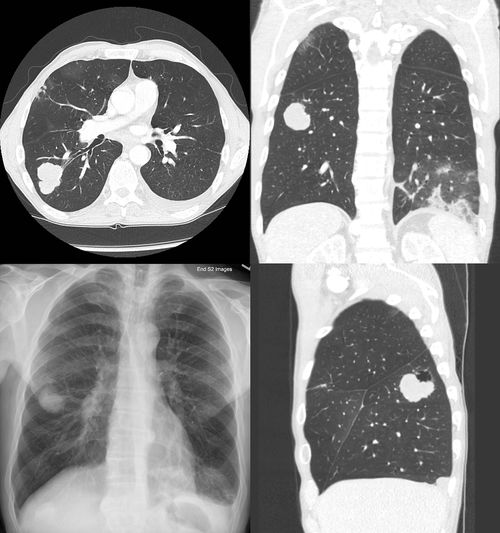

需要区分的是,“肺部肿瘤4cm”通常指的是肺癌,但在发现肺部占位时,首先要通过影像学、甚至病理活检来确定性质,肺部发现的结节(Nodule)可能是良性的(如炎症、真菌球、肉芽肿等),也可能是恶性的(肺癌),只有经过病理学检查确认为恶性肿瘤,才能称之为肺癌,并进行分期。

发现肺部有一个4厘米的肿瘤,不必过度恐慌,但务必及时就医,进行全面的检查评估,医生会通过详细的病史、体格检查、影像学(如CT、PET-CT)、可能的支气管镜检查、甚至经皮穿刺活检等手段,综合判断肿瘤的性质(良性或恶性)、T分期、N分期和M分期,最终确定一个准确的临床分期。